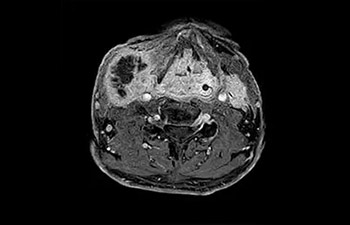

Lumbale kanaalstenose

met Compressed SENSE